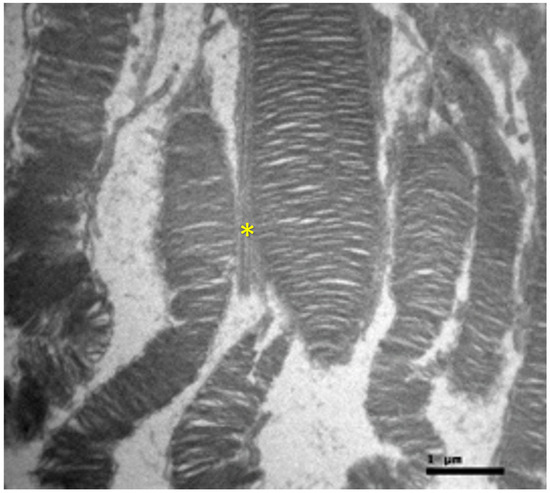

Background/Objectives: Cisplatin is a potent chemotherapeutic agent whose clinical utility is limited by severe side effects, including neurotoxicity affecting the ocular system. The pathophysiology involves oxidative stress and mitochondrial dysfunction, to which the retina is particularly vulnerable. Selenium (Se), an essential trace element and component of antioxidant enzymes, has shown potential in mitigating cisplatin toxicity, although its efficacy with respect to retinal structure and the influence of administration routes remain underexplored. This study aimed to evaluate the protective efficacy of selenium against cisplatin-induced retinal toxicity and compare the effects of intraperitoneal and oral selenium administration. Methods: Forty adult male Wistar rats were randomized into four groups (n = 10 each): Group A (Cisplatin Monotherapy, 3.5 mg/kg IP for 5 days; cumulative dose 17.5 mg/kg); Group B (Cisplatin + Intraperitoneal Selenium, 2.73 mg/kg; cumulative dose 60 mg/kg); Group C (Control); and Group D (Cisplatin + Oral Selenium). Selenium prophylaxis, administered as sodium selenite (Na2SeO3), began two days prior to cisplatin administration and continued for 15 days post-treatment. Retinal evaluation two weeks after cisplatin cessation included light microscopy, semi-quantitative immunohistochemical (IHC) analysis for inflammatory (IL-6) and fibrotic (TGF-β2) markers, and Transmission Electron Microscopy (TEM) for ultrastructural analysis, which were the primary endpoints. Statistical differences in the IHC scores were analyzed via the Kruskal‒Wallis H test with Dunn’s post hoc comparisons. Results: Cisplatin monotherapy (Group A) caused severe disruption of the retinal architecture, including edema, reactive gliosis, and significant upregulation of IL-6 and TGF-β2. Ultrastructural analysis revealed mitochondrial swelling (cristolysis) and photoreceptor disk fragmentation. Intraperitoneal selenium (Group B) was associated with significant structural preservation and intact mitochondria, with TGF-β2 levels comparable to those of the controls, although the IL-6 level remained moderately elevated. Conversely, oral selenium (Group D) suppressed both IL-6 and TGF-β2 expression to near-negative levels but provided less ultrastructural protection, resulting in persistent mitochondrial swelling and focal photoreceptor disruption. Conclusions: Systemic cisplatin induces severe subcellular retinal toxicity characterized by mitochondrial damage and photoreceptor degeneration. Selenium supplementation attenuates these effects; however, outcome patterns differ by administration route. Intraperitoneal selenium was associated with greater morphological and ultrastructural preservation despite persistent IL-6 elevation, whereas oral selenium normalized immunohistochemical marker expression to near-control levels but was associated with more pronounced residual subcellular damage on qualitative TEM assessment. These preliminary morphological and immunohistochemical findings suggest that the route of selenium delivery may influence its neuroprotective profile; however, pharmacokinetic measurements and functional retinal assessments, such as electroretinography, are warranted before its clinical translation. Full article